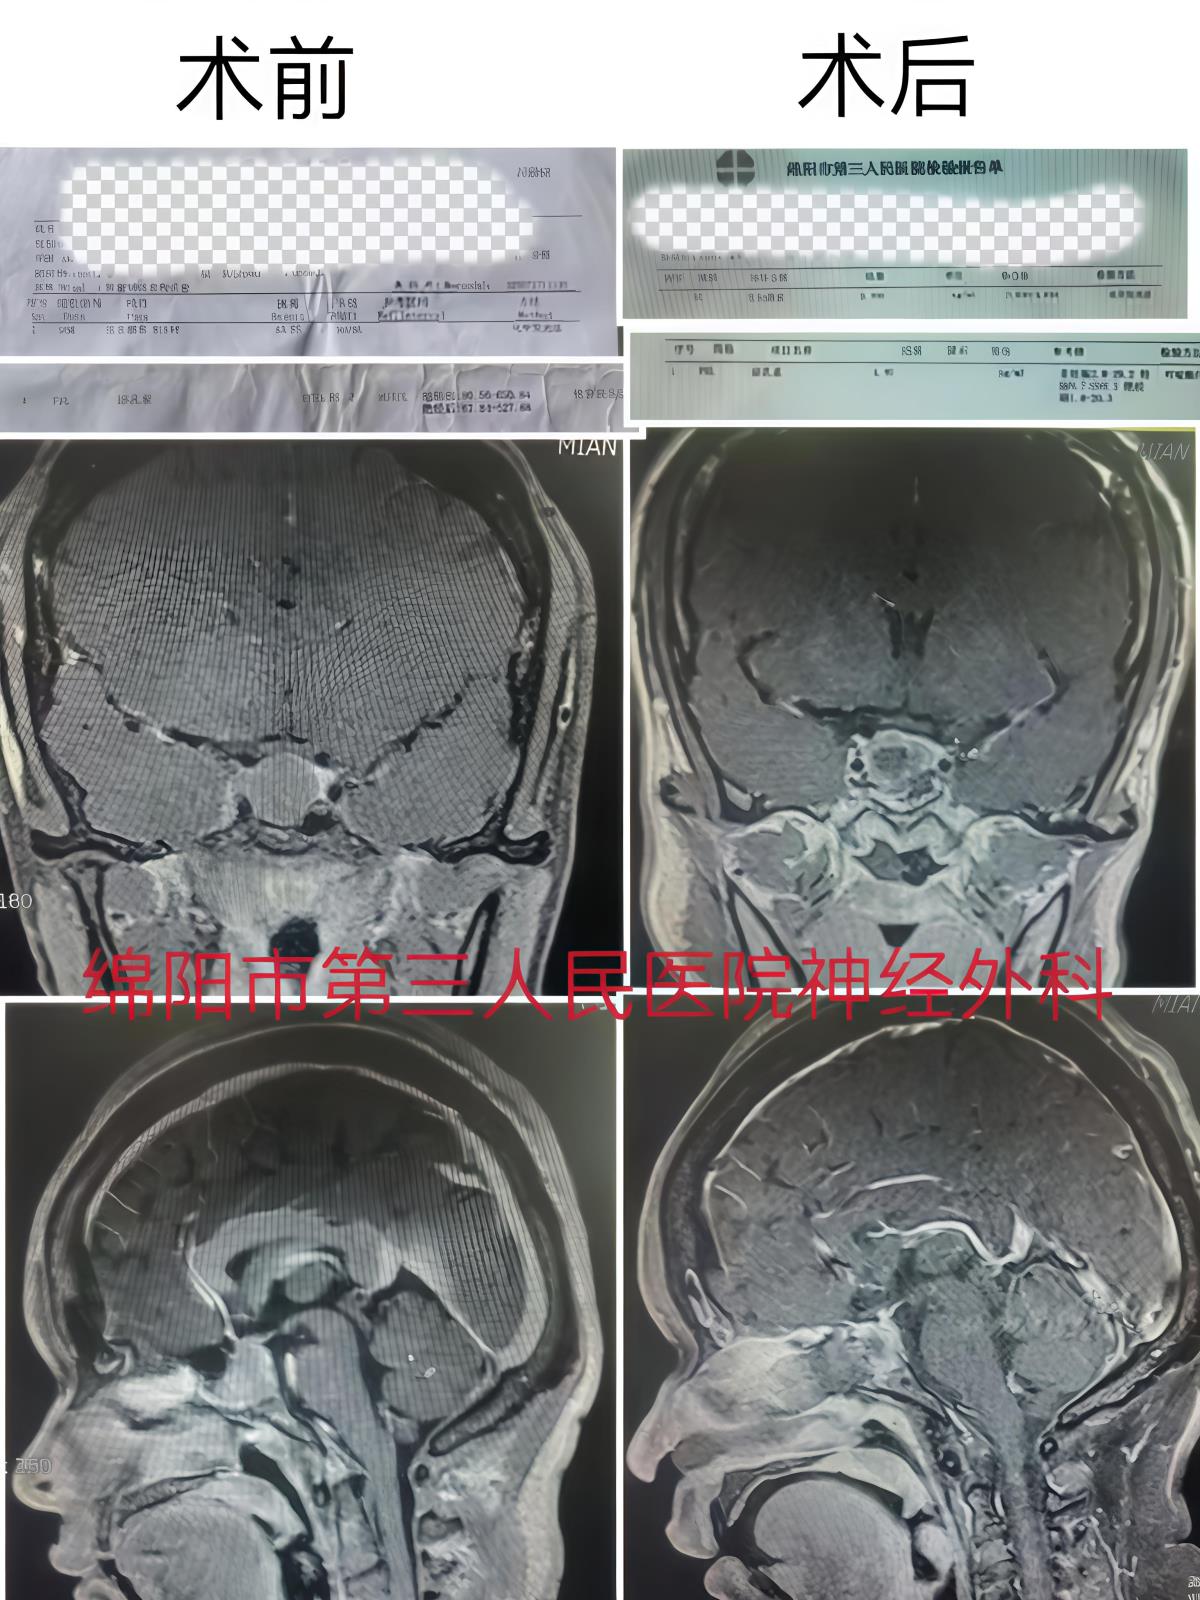

近日,绵阳三医院神经外科团队为一名肢端肥大面容明显的中年女性,实施神经内镜下经鼻蝶切除肿瘤及受累右侧海绵窦内侧壁的手术。

据悉,朱女士(化名)于3年前就在其他医院查出“鞍区病变”,因对生活、工作未造成影响就未进行系统的治疗。最近,其自觉肢体麻木加重,手足进一步增粗,就连鞋码都增大了。再次检查: 生长激素、泌乳素均明显升高,考虑垂体生长激素泌乳素混合腺瘤,knosp3级。为进一步治疗,遂来到绵阳三医院神经外科寻求帮助。

神经外科学科带头人刘阳主任医师与神经外科肿瘤组组长金彪主治医生根据患者综合情况讨论后,决定为患者实施经鼻蝶神经内镜下病变部位切除术。患者术后检查:生长激素、泌乳素均降至正常。现患者已康复出院!